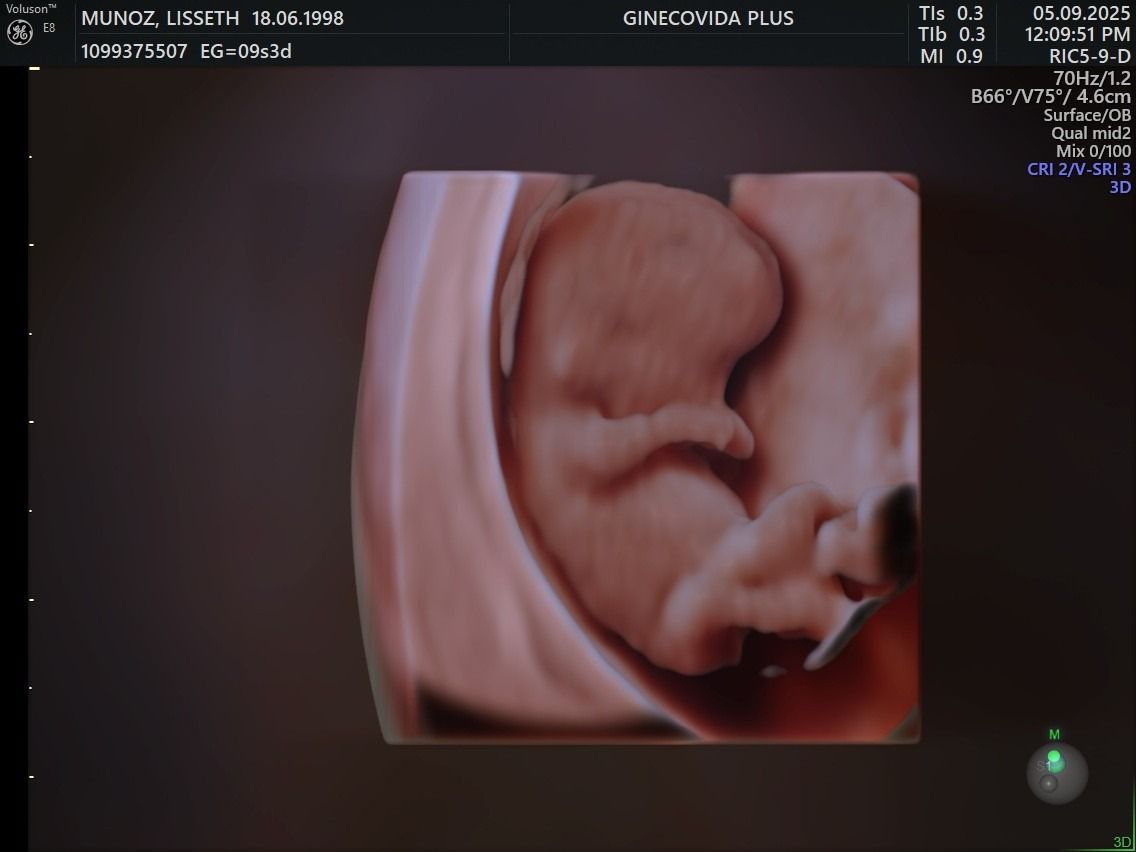

UN DULCE MILAGRO VIENE EN

CAMINO, ACOMPÁÑANOS A

CELEBRAR LA LLEGADA DE

NUESTRO PEQUEÑO TYLER dino gif